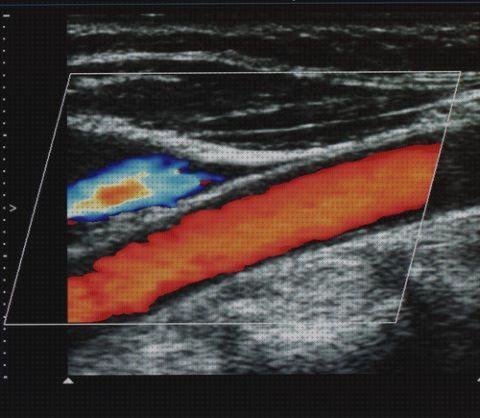

Una ecografía doppler es una investigación por imágenes que emplea ondas de sonido para exhibir la circulación de la sangre por los vasos sanguíneos. Las ecografías comunes también utilizan ondas de sonido para hacer imágenes de construcciones internas del cuerpo, pero no pueden exhibir la sangre en circulación.

La ecografía doppler funciona buscando ondas sonoras que se demuestran en objetos en movimiento, como los glóbulos rojos. Esto se le conoce como producto doppler.

Con esta prueba se están estudiando varios factores del flujo sanguíneo. Su rapidez, sitio, dinero, etcétera. Todos ellos vienen dados en diferentes unidades de medida. Sin embargo, los valores normales de ésas medidas dependen de la zona del cuerpo a analizar. Lo que es un flujo normal en corazón puede ser que sea enfermo en las carótidas u algunos otros zonas. Por aquello lo desenlaces deben estudiarse a conocimiento.

Es común que con los resultados se entregue alguna imagen, aunque si no lo realizan no tienes que preocuparte porque no suele valer de mucho. En la imagen verás la típica serie de grises que se están viendo dentro de una ecografía normal, pero con áreas de colores. Esos colores representan el flujo sanguíneo desde el rojo al celeste. El rojo indica que el flujo va hacia la sonda del ecógrafo (cuanto más grande más rápida es), y el celeste que se aleja (cuanto más grande más rápido se aleja). El blanco o amarillento suele denotar un flujo más lento o estable.